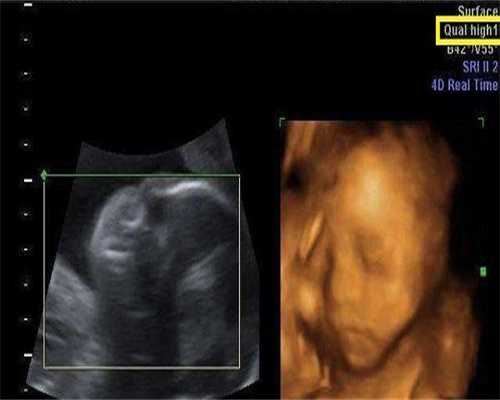

为您解析厦门试管助孕HRT冻胚移植时间如何科学确定,错过最佳窗口期怎么办?提供详细的方案、应对策略和补救措施,助力代生、代怀家庭成功。

激素替代治疗(HRT)方案中,冻胚移植时间的确定需通过多维度评估,以保障厦门试管助孕的成功率。这对于考虑代生或代怀的家庭尤为重要。

从月经周期第2-3天开始补充雌激素(口服/阴道给药),通过超声监测使内膜厚度达7-14mm。典型案例中,32岁患者通过14天雌激素补充使内膜从5mm增长至9mm。这是代生过程中关键的一步。

当内膜达标后,开始补充孕酮模拟黄体期。通常在孕酮使用后3-5天进行移植,此时子宫内膜呈现典型三线征,雌二醇水平维持在200-300pg/ml。成功的代怀离不开精细的激素调控。

囊胚移植选择孕酮第5天,卵裂期胚胎则选择第3天。某生殖中心数据显示,这种同步策略使临床妊娠率提升至65%。了解这些细节有助于优化代生的整个流程。